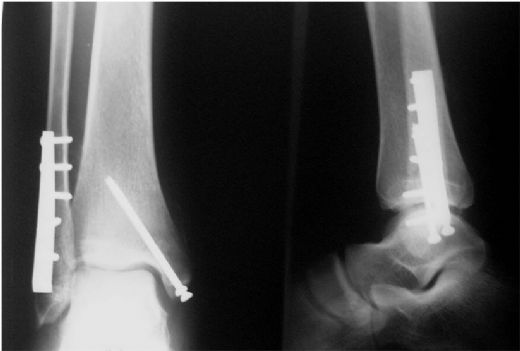

Ameliyat YöntemleriAyak bileği kıkırdak ameliyatında kullanılan çeşitli teknikler bulunmaktadır. Bu teknikler, hasarın boyutuna ve hastanın genel sağlık durumuna göre seçilir. Temel ameliyat yöntemleri şunlardır:

Ameliyat Öncesi DeğerlendirmeAyak bileği kıkırdak ameliyatı, kapsamlı bir değerlendirme sürecini gerektirir. Bu aşamada doktor, hastanın tıbbi geçmişini gözden geçirir ve fizik muayene yapar. Ayrıca, aşağıdaki görüntüleme yöntemleri kullanılabilir: